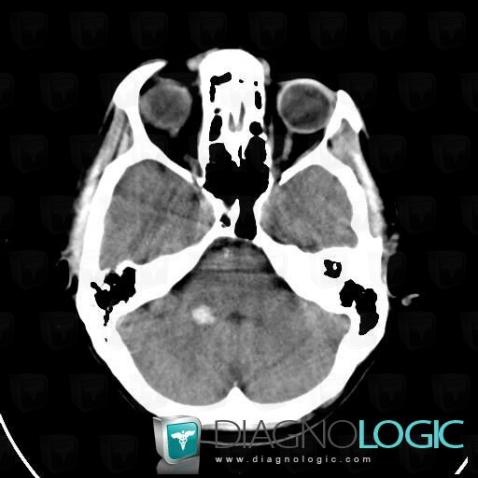

Cavernous angioma, Brainstem, Posterior fossa, CT

Here is the specific information in the key image above:

- Diagnosis Cavernous angioma, Location(s) Posterior fossa, with gamuts Hyperdense infratentorial lesion on noncontrast CTBrainstem, with gamuts Brainstem lesion